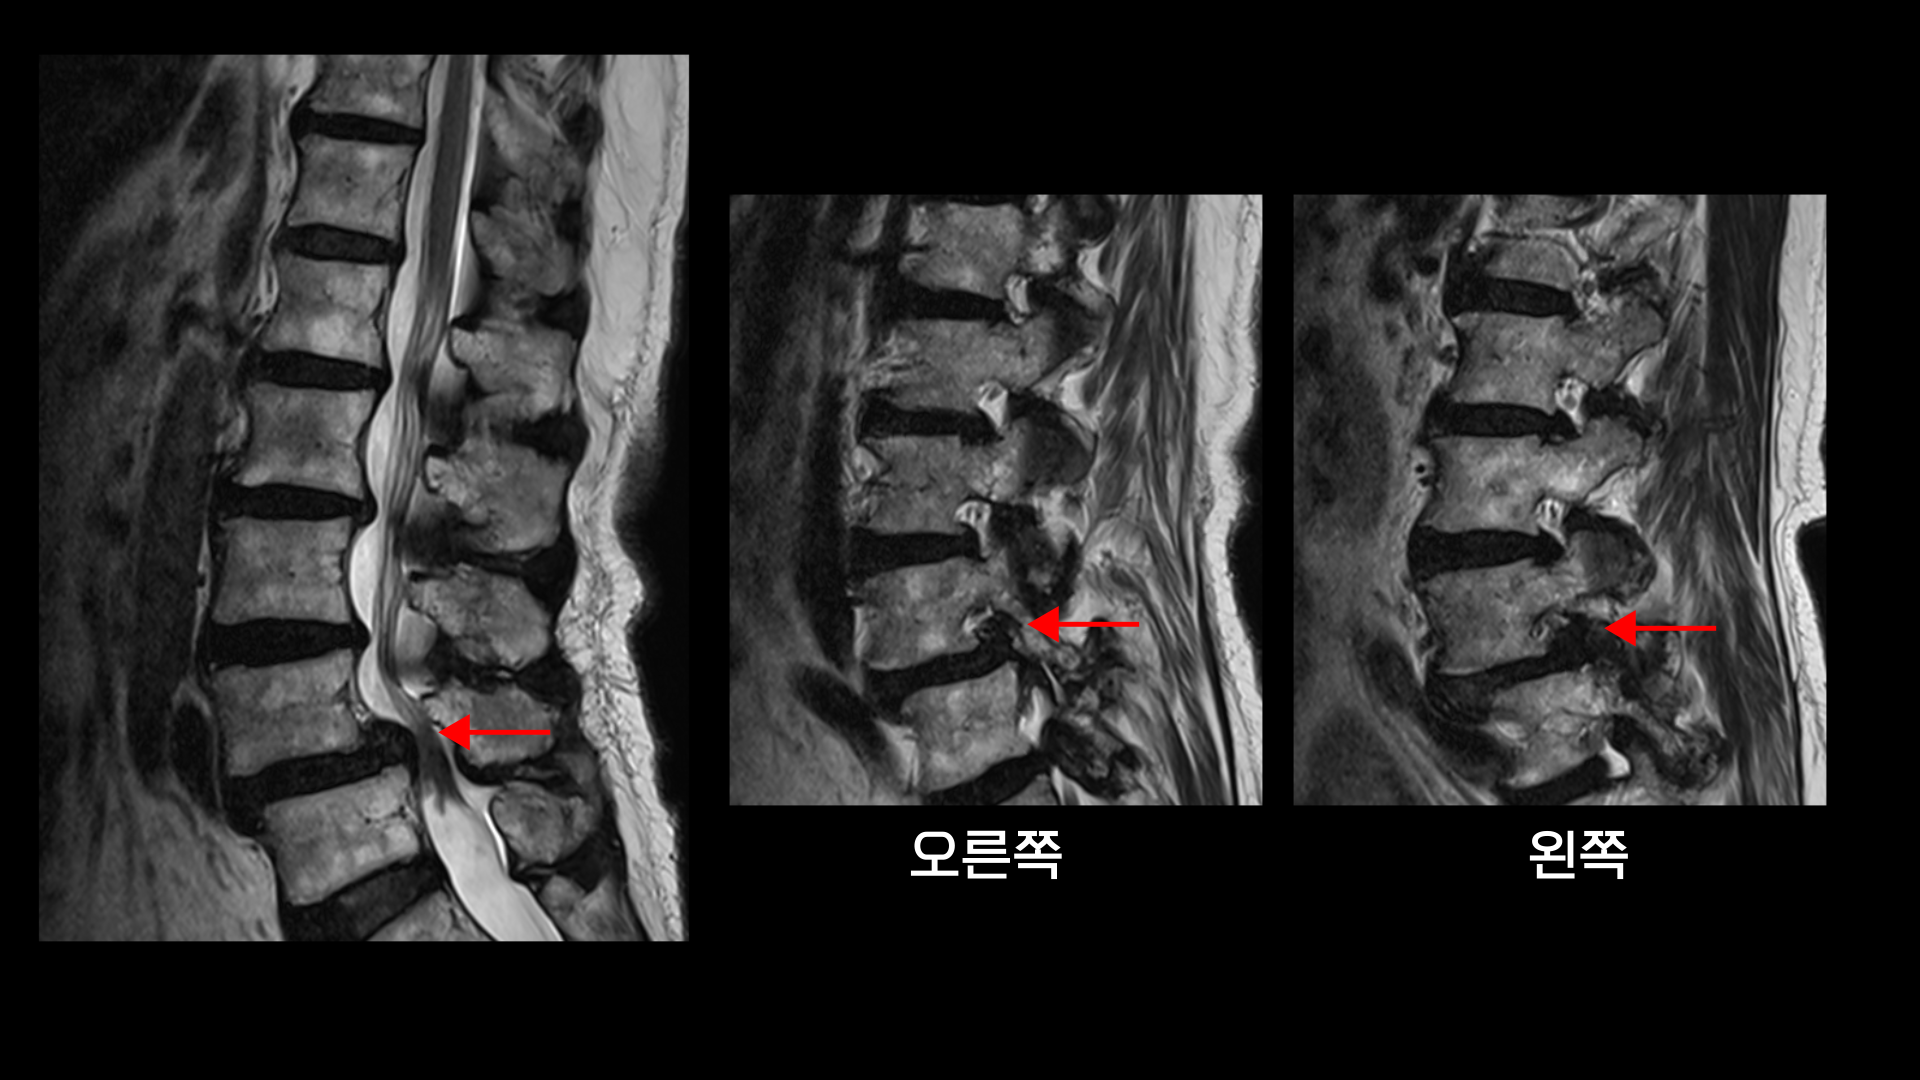

이 환자분 상태를 먼저 설명 드린 후 이분 말씀을 들어보겠습니다. 이분은 협착증을 앓으신 지 약 7년 정도 되셨습니다. MRI를 보면 여러 마디에 퇴행성 디스크가 있고

4번, 5번에는 전방전위증이 있습니다.

전방전위증이 있는 4번, 5번 마디에서는 오른쪽, 왼쪽 신경가지가 나가는 양쪽 추간공이 모두 좁아져 있고

그리고 척추관도 황색인대가 심하게 두꺼워지면서 중심성 협착도 매우 심합니다.